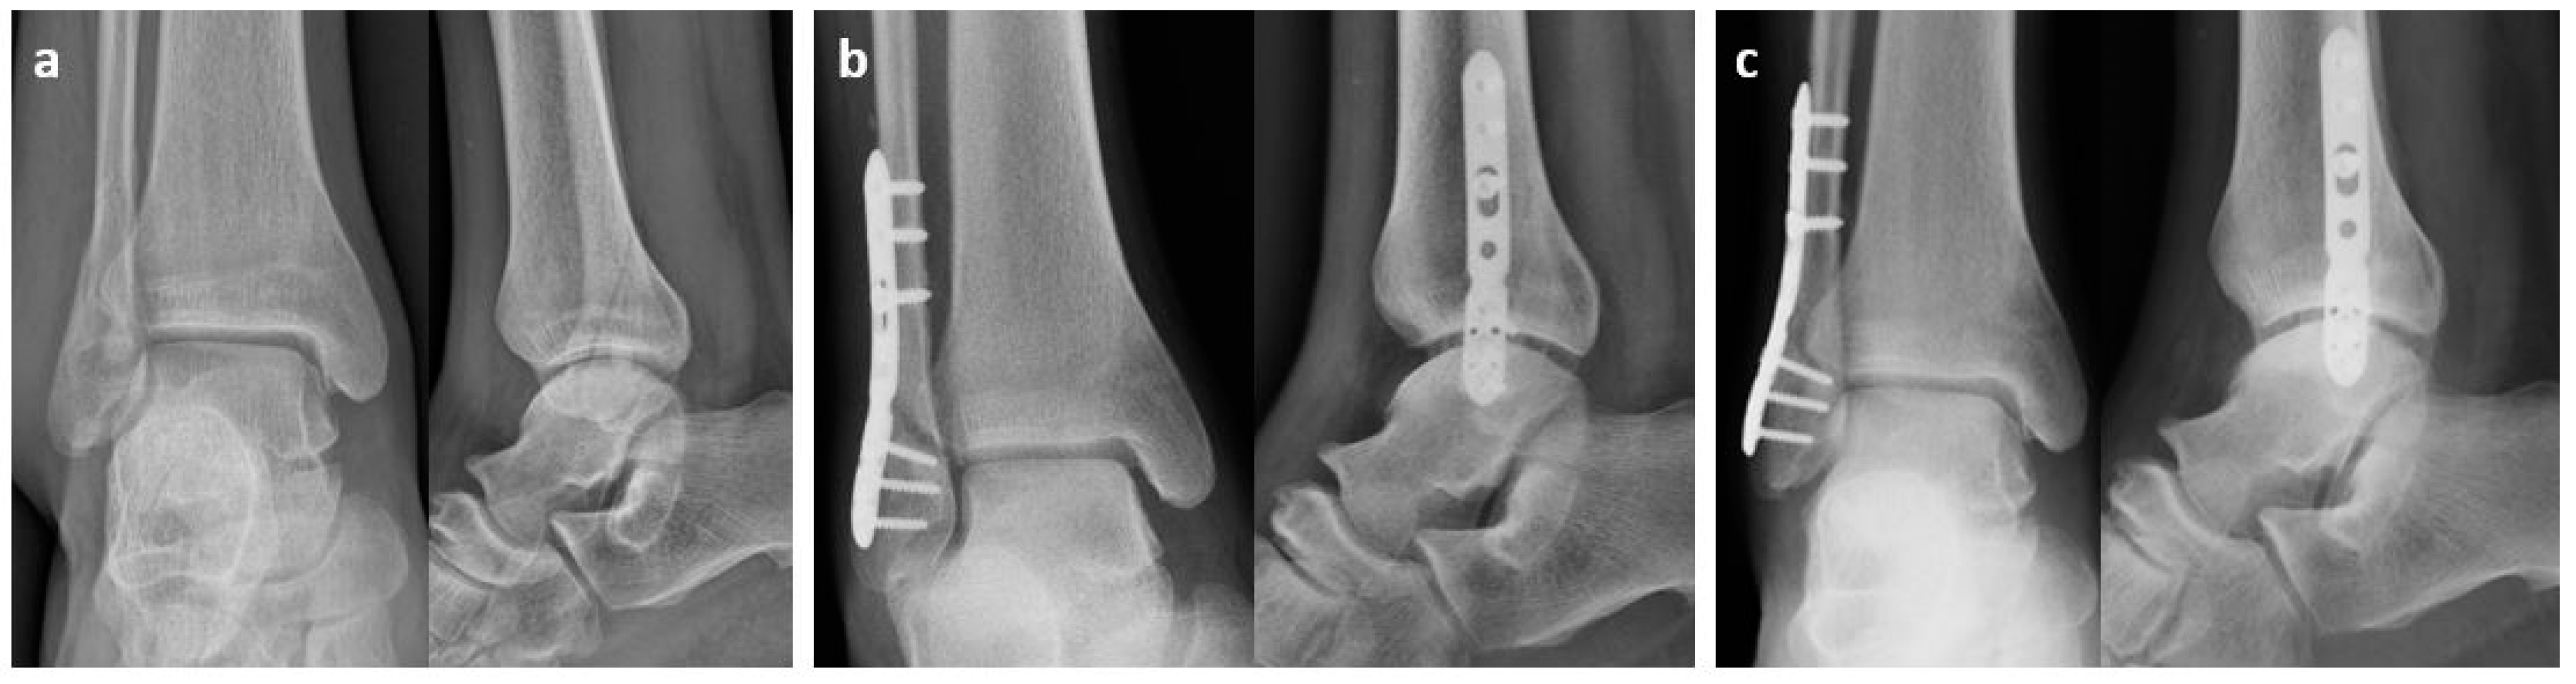

2.1. Surgical Procedure